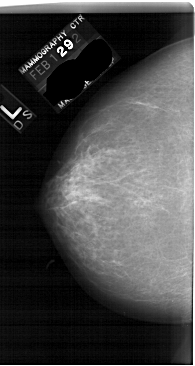

A_1739_1.LEFT_CC

LEFT_CC LINES 6571 PIXELS_PER_LINE 3496 BITS_PER_PIXEL 12 RESOLUTION 43.5 NON_OVERLAY